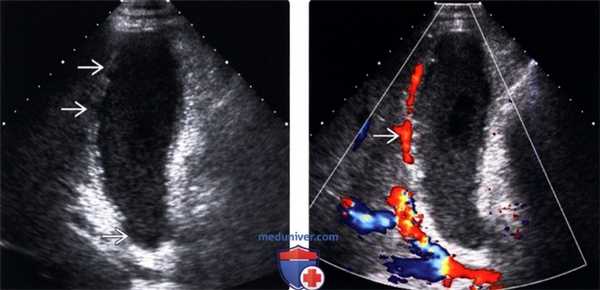

(Левый) На продольном косом УЗ срезе у пациента с острым веска менным холециститом с гангреной, перенесшего трансплантацию легкого, визуализируется растянутый желчный пузырь, содержащий вязкий сладж. Стенка желчного пузыря утолщена, ее контур имеет дефекты.

(Правый) На продольном косом срезе у того же пациента определяется гиперемия перипузырной зоны, признаки кровотока в некротизированной стенке отсутствуют.